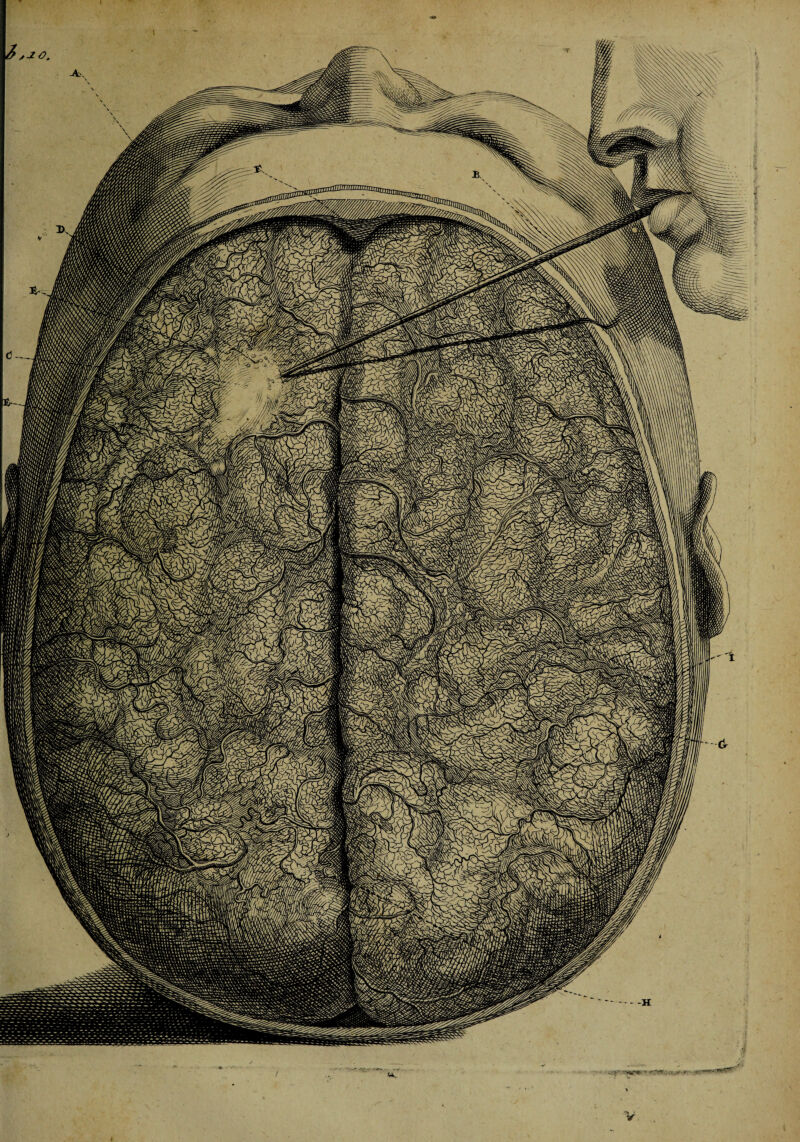

Epistola anatomica, problematica nona / Authore Andrea Ottomaro Goelicke ... ad virum clarissimum Fredericum Ruyschium [With his reply] ... De cursu arteriarum per piam matrem cerebrum involventem, de tertia cerebri meninge, de arteriis membranarum cavitates ossis frontis supra narium radices & eassub sella equina investientium, nec non de vasis arteriosis novis hepatis & diaphragmatis.

13/14 (page 13)